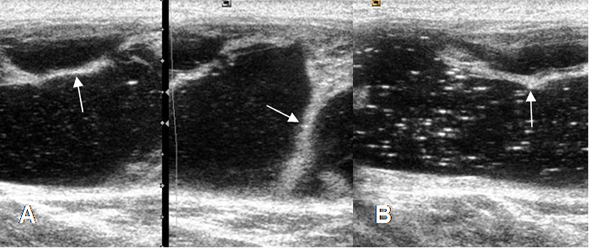

Se identifica en la ecografía, como una lesión posterior y comunicada en la cavidad articular. Puede tener contenido anecoico, hipoecoico o de ecogenicidad mixta y se relaciona con los músculos. (9). (Fig 175A y 175B).

Fig 175 B. Quiste de Baker complicado.

A y B: Ecografías. Lesión de consistencia líquida en la fosa poplítea, con septos gruesos (flechas) y ecos internos, por sangrado sobre-infección o alto contenido de proteínas, que corresponde a quiste de Baker complicado.